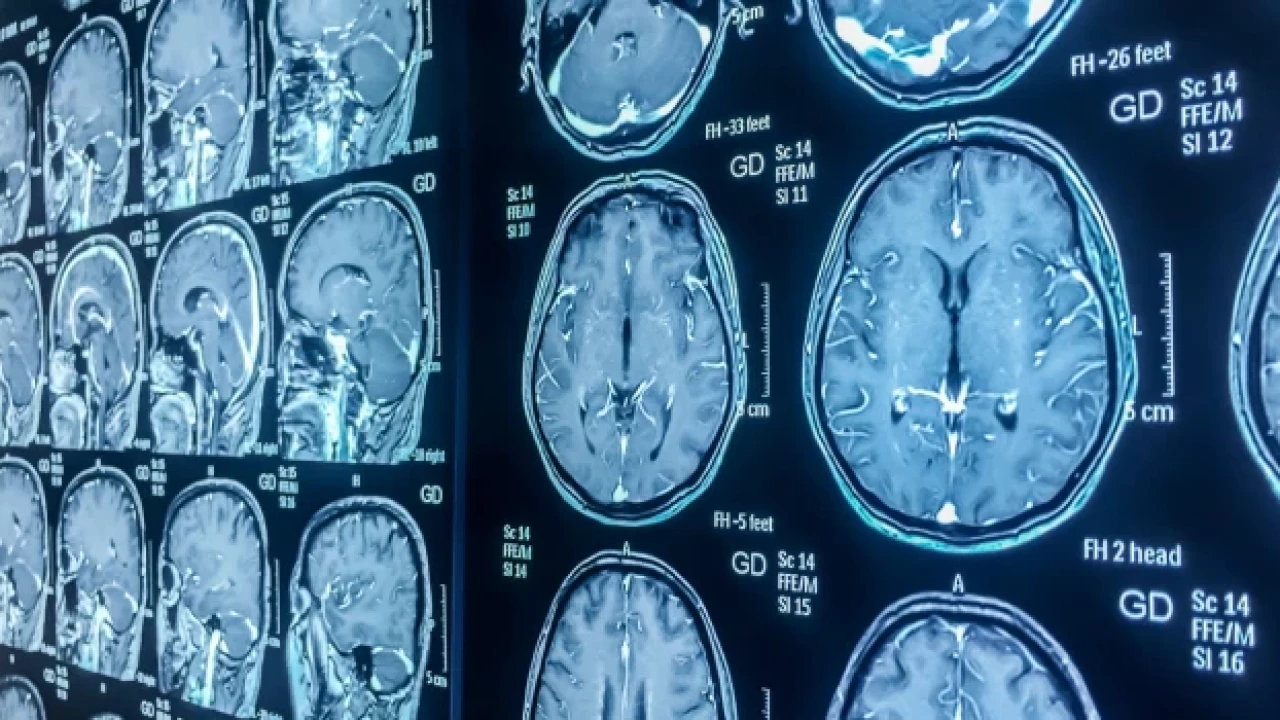

Muhalif. SAĞLIK Beyin kanseri, kan testi ile erken teşhis edilebilecek

Beyin kanseri, kan testi ile erken teşhis edilebilecek

Bilim insanları, beyin kanserini erken evrede tespit etmek için dünyada ilk kez geliştirilen bir testin tanıda devrim yaratabileceğini, tedaviyi hızlandırabileceğini ve hayatta kalma oranlarını artırabileceğini açıkladı.

İngiltere'de bir araştırma ekibi, beyin kanserinin en ölümcül türlerine sahip hastaların bile çok daha hızlı teşhis edilmesine yardımcı olabilecek, potansiyel olarak onları invaziv ve yüksek riskli cerrahi biyopsilerden koruyabilecek basit bir kan testi tasarladı. Buluş, Uluslararası Kanser Dergisi'nde bildirildi.

Testin özellikle "erişilemez" beyin tümörleri olan ve tedaviye mümkün olan en kısa sürede başlamanın hayati olduğu hastalar için faydalı olacağı bildirildi.

Imperial College sağlık hizmetleri tarafından yönetilen Beyin Tümörü Araştırma Merkezi'ndeki araştırmacılar, testin, en sık teşhis edilen yüksek dereceli beyin tümörü türü olan glioblastoma (GBM) dahil olmak üzere bir dizi beyin tümörünü doğru bir şekilde teşhis edebildiğini açıkladı. Ekip, testin "yüksek analitik hassasiyete ve kesinliğe" sahip olduğunu bildirdi.

Beyin Tümörü Araştırmaları kuruluşunun genel müdürü Dan Knowles"Bu çığır açıcı araştırma, beyin tümörü hastalarında daha erken tanıya ve daha iyi sonuçlara yol açacak. Sonuçları doğrulamak için daha fazla araştırma yapmayı planlıyoruz ve eğer başarılı olursak hastalar iki yıl gibi kısa bir sürede yeni testten faydalanabilecek" dedi.

Datar Cancer Genetics'in finansmanıyla geliştirilen TriNetra-Glio kan testi, tümörden kurtulan ve kanda dolaşırken bulunan glial hücreleri izole ederek çalışıyor. İzole edilen hücreler daha sonra boyanarak mikroskop altında tanımlanıyor.

Beyin Tümörü Araştırma Merkezi'ni yöneten Dr. Nelofer Syed şunları söyledi:

“Bu teknoloji sayesinde ulaşılması mümkün olmayan tümörlerin tanısı, risksiz ve hasta dostu bir kan testiyle mümkün hale gelebiliyor. Şu anda bu tür tümörler için invaziv olmayan veya radyolojik olmayan testler olmadığından bunun dünyada bir ilk olacağına inanıyoruz."